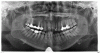

Тарасова Опубликовано 20 октября, 2012 Поделиться Опубликовано 20 октября, 2012 Здравствуйте, уважаемые специалисты!Прошу прощения у модераторов форума, что размещаю пост в рубрике "терапия", более подходящей рубрики не нашла. Зубы никогда не болели, за исключением нижней шестерки слева, которую, как вы видите, я потеряла. Справа вверху от рождения нет резца – это меня это не беспокоит.Все зубы лечились вовремя, не являются подвижными, с терапевтической точки зрения проблем нет (проверяюсь каждые полгода).Что касается десен, - они никогда не болели, не кровоточили и не воспалялись. Дважды в день, после чистки зубов, пользуюсь ирригатором полости рта. Зубные отложения снимала около года назад.Несмотря на отсутствие жалоб, я посетила пародонтолога. Потому что мне 44 года, и я знаю, что с возрастом у многих начинаются проблемы с костной тканью. Вердикт врача после того, как она увидела снимок, стал для меня неожиданностью: пародонтит средней степени. Она сказала, что профессиональной гигиеной полости рта тут не обойтись, и, если я не хочу лишиться зубов, мне надо раз в полгода проходить месячный курс лечения!Я не стану ставить под сомнение профессионализм этого доктора, но хотелось бы выслушать мнение других врачей: неужели есть необходимость в таком долгом и дорогостоящем лечении? Ссылка на комментарий

Ром@н Опубликовано 20 октября, 2012 Поделиться Опубликовано 20 октября, 2012 пере лечить все и даже 2.6, 4.6 скорее под удаление. что видно на оптг все усугубляет ваш диагноз в отношении пародонтита Ссылка на комментарий